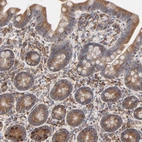

Immunohistochemistry analysis in human thyroid gland and skeletal muscle tissues using HPA003230 antibody. Corresponding PDIA3 RNA-seq data are presented for the same tissues.